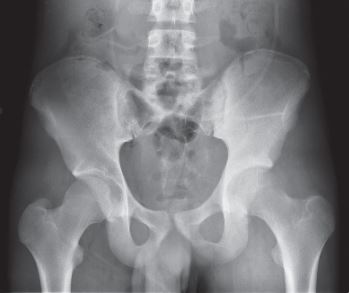

The pelvis is a common site for malignant and benign tumors to arise. The pelvis is composed of three parts; the ischium, illium, and pubis. The socket (hip joint) is called the acetabulum which forms the “cup.” Common primary sarcomas that can arise from the pelvis include osteosarcoma, Ewing’s Sarcoma, and chondrosarcoma. Soft tissue malignant tumors can sometimes involve the pelvis as well. Additionally, metastatic disease can commonly spread to the pelvis. Limb-sparing surgery can be performed for approximately 95% of tumors arising from the pelvis. In some instances the extremity cannot be saved and an amputation is performed.

You will be monitored periodically with X-rays over the course of 5 years. Sometimes an MRI and/or CT may be used to additionally monitor the area to make sure the tumor has not come back. You will then have follow up appointments every 4 months for the first 2 years, then every 6 months for the next 2 years, and then once a year. Since the bone integrity has been restored to full or almost full, recovery is anticipated provided the patient adheres to strict physical therapy.